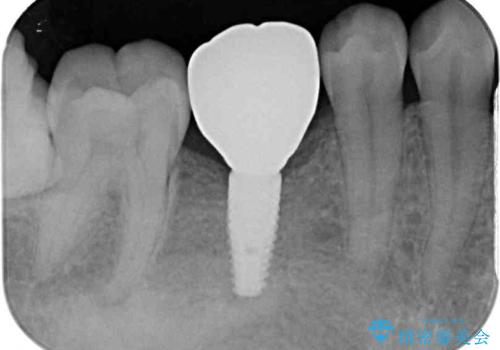

空いている時間を利用して通院 奥歯のインプラント治療

- 大学病院でインプラント治療を進めていたものの、予約のタイミングが合わないとのことで来院された患者様です。

欠損部位の骨や歯肉の状態は非常に良く、速やかにインプラント埋入を行い、補綴治療を進めて行くことのできる状態でした。

当院の予約も空きはあまりないのですが、キャンセルが出たタイミングなどをうまく活用し、速やかに進めて行くこととしました。

平日の昼間でもご来院可能とのことであったので、必要最小限の期間で治療を終えることができました。